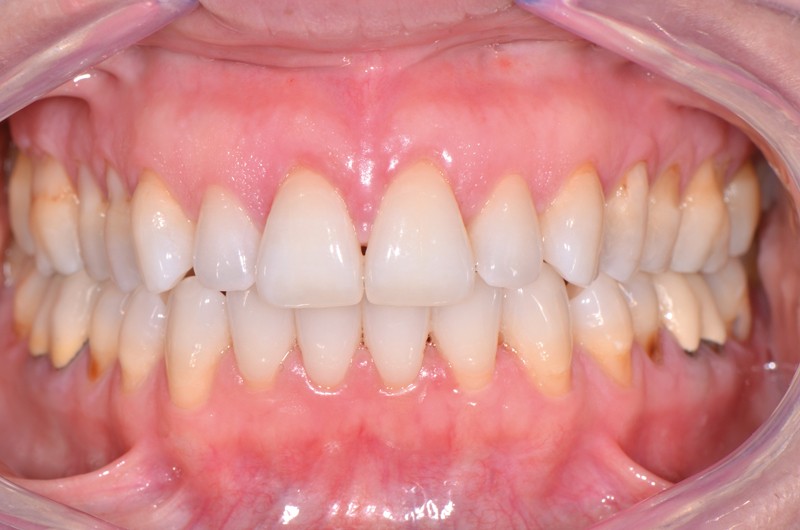

L’examen clinique révèle un biotype de type III et IV de Maynard et Wilson [1], dans les secteurs latéraux, une inflammation modérée en corrélation avec des dépôts supra-gingivaux et des restaurations débordantes, l’absence de poches parodontales, des pertes papillaires de classe I de Nordland et Tarnow [2] et des récessions gingivales associées à des lésions cervicales d’usure non carieuses et carieuses (35/45) majoritairement comblées par des restaurations en résine composite (fig. 1).

La patiente présente une parodontite chronique modérée généralisée stabilisée [4]. Étant donné la perte d’attache interproximale, les récessions sont de classe III de Miller [5] ou RT2 de Cairo [6] associées à des lésions cervicales d’usure.

L’étiologie directe de ces atteintes tissulaires est la technique de brossage traumatogène sur un biotype parodontal fin, donc à risque et prédisposant aux récessions gingivales [1, 7].